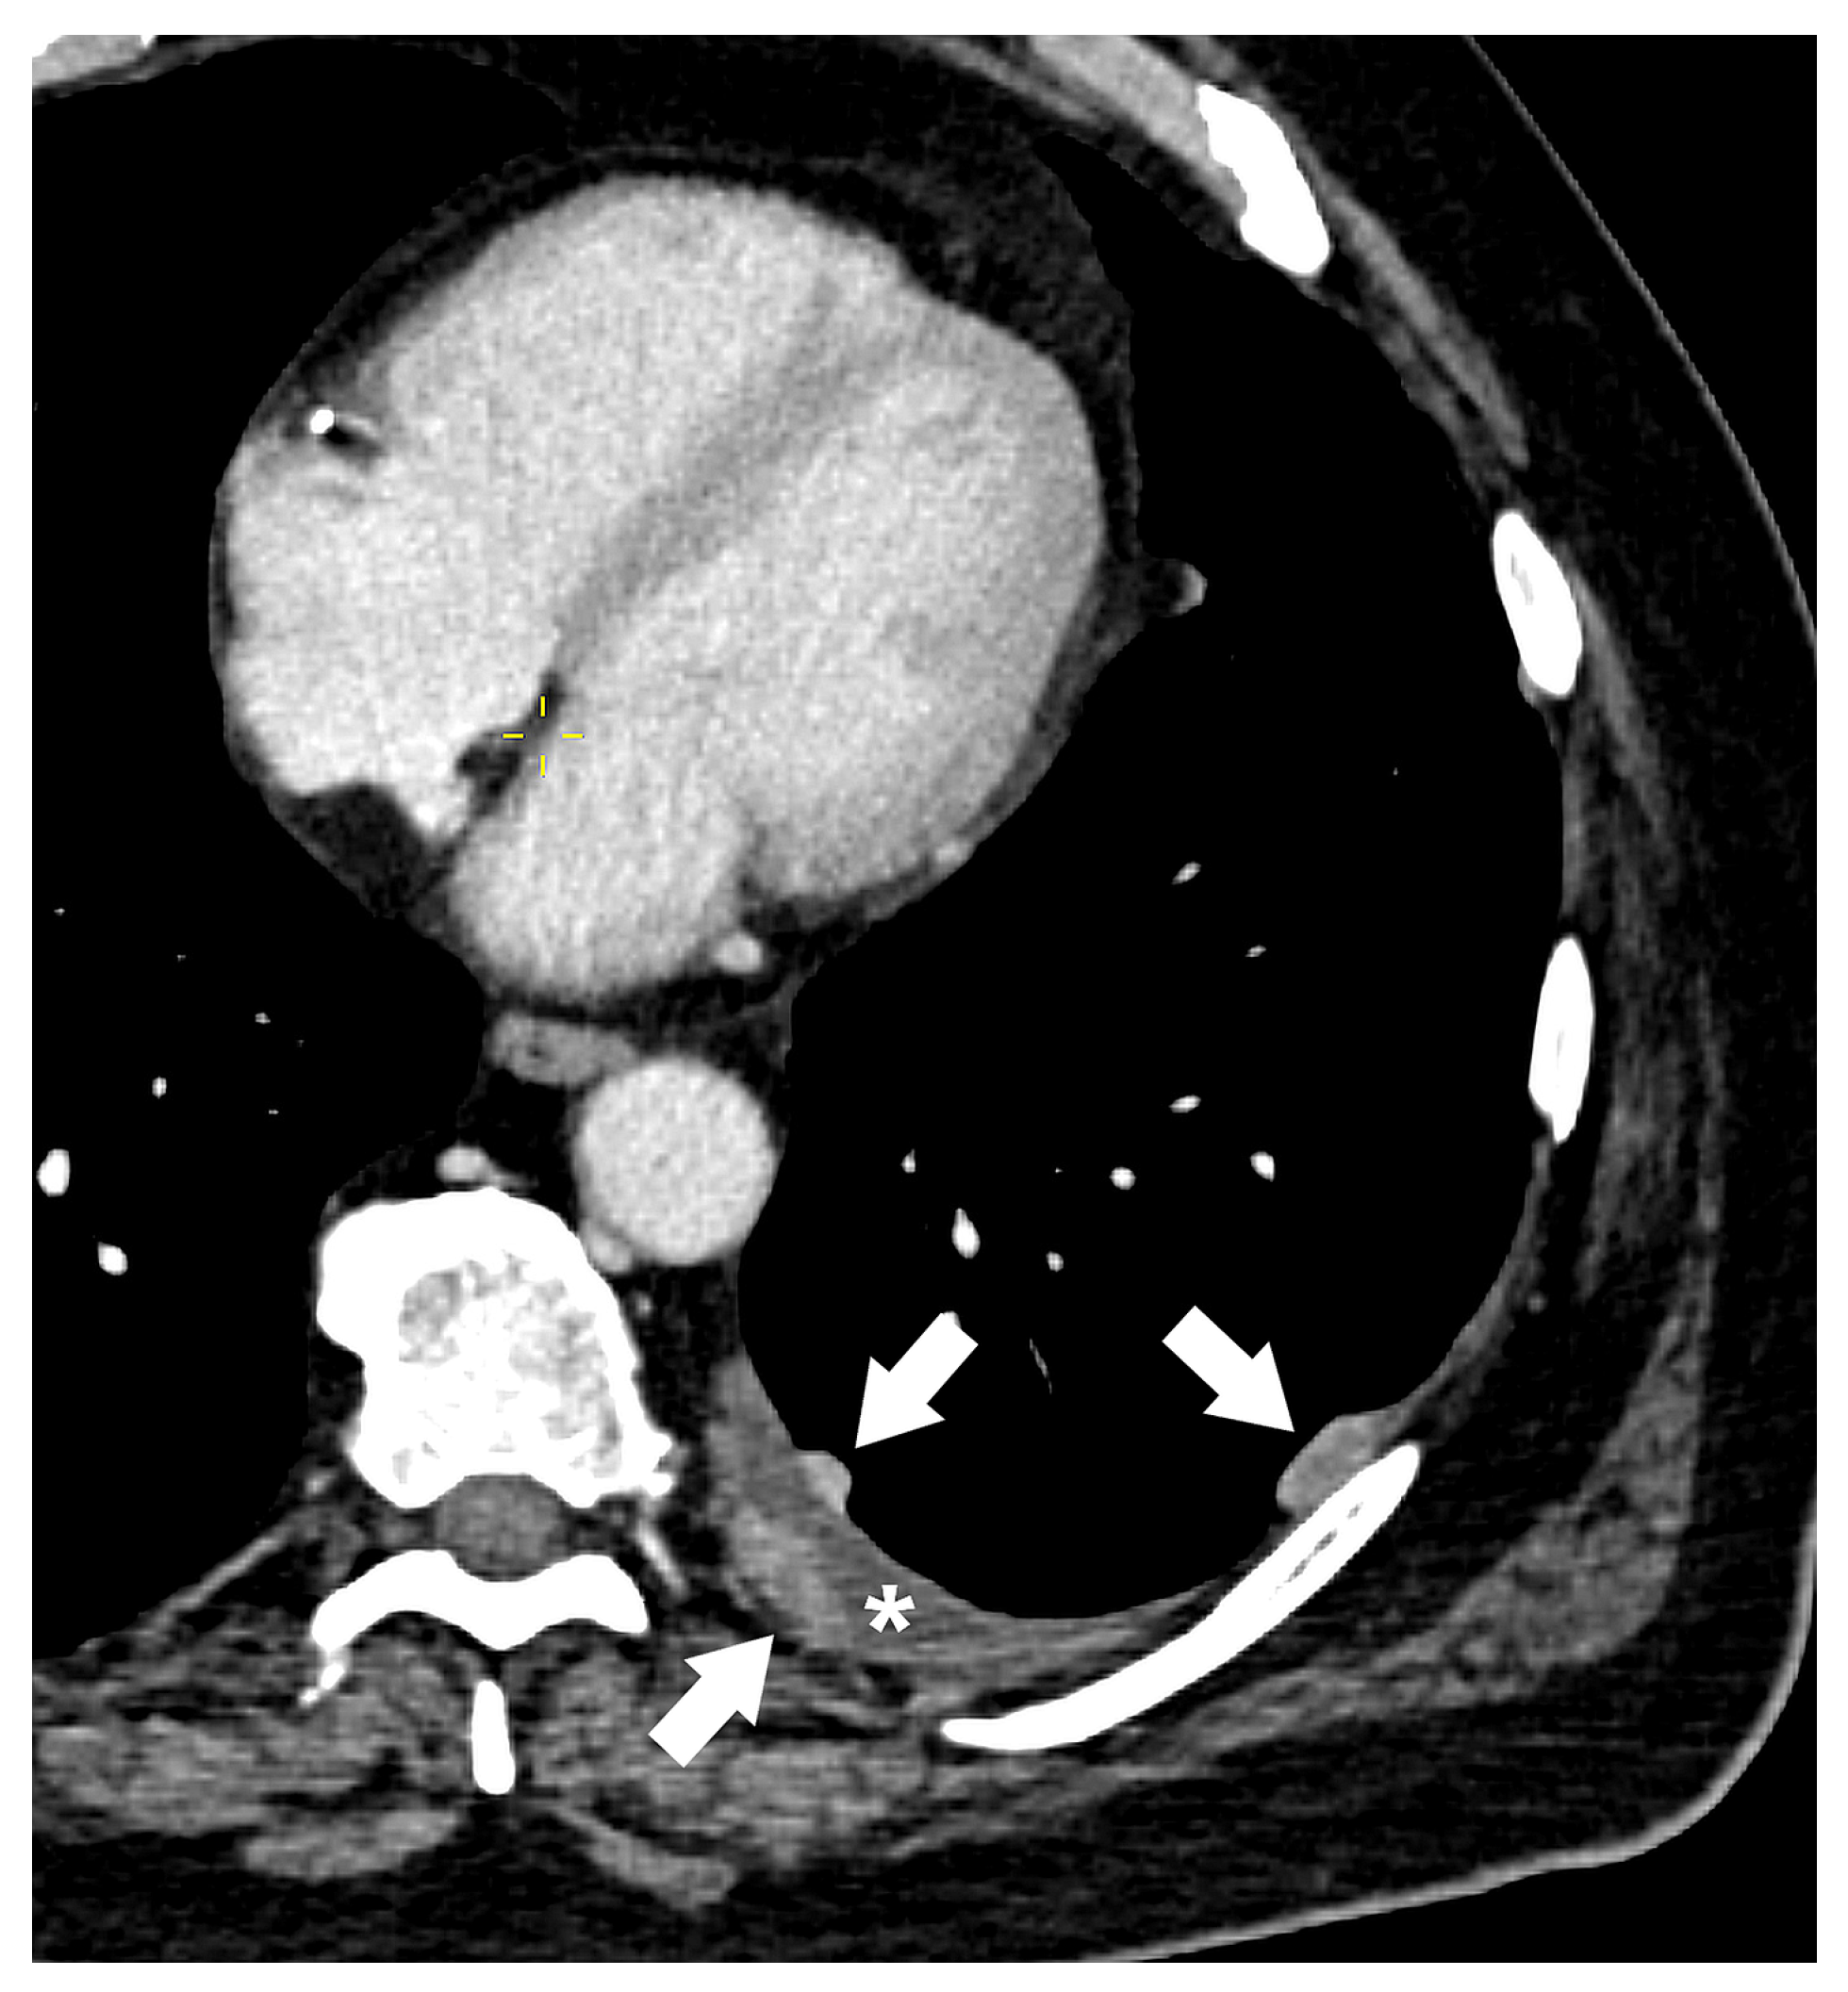

| T4 | Tumor > 7 cm in the greatest dimension Invasion of the mediastinum, thymus, trachea, carina, recurrent laryngeal nerve, vagus nerve, esophagus, or diaphragm Invasion of the heart, great vessels (aorta, superior or inferior vena cava, intrapericardial pulmonary arteries or veins), supra-aortic arteries, or brachiocephalic veins Invasion of subclavian vessels, vertebral body, lamina, spinal canal, cervical nerve roots, or brachial plexus Separate tumor nodule(s) in a different ipsilateral lobe than that of the primary | Signs of mediastinal invasion: infiltration of the mediastinal fat or structures that indicate the T4 stage, tumor–mediastinum contact length of more than 3 cm, an obtuse angle between the tumor and the mediastinum [37] Signs of vascular invasion: disappearance of the fat layer between the mass and the vessel, the angle between the mass and vessel wall >90°, a stenosis or deformation of the vascular lumen [41,42] |